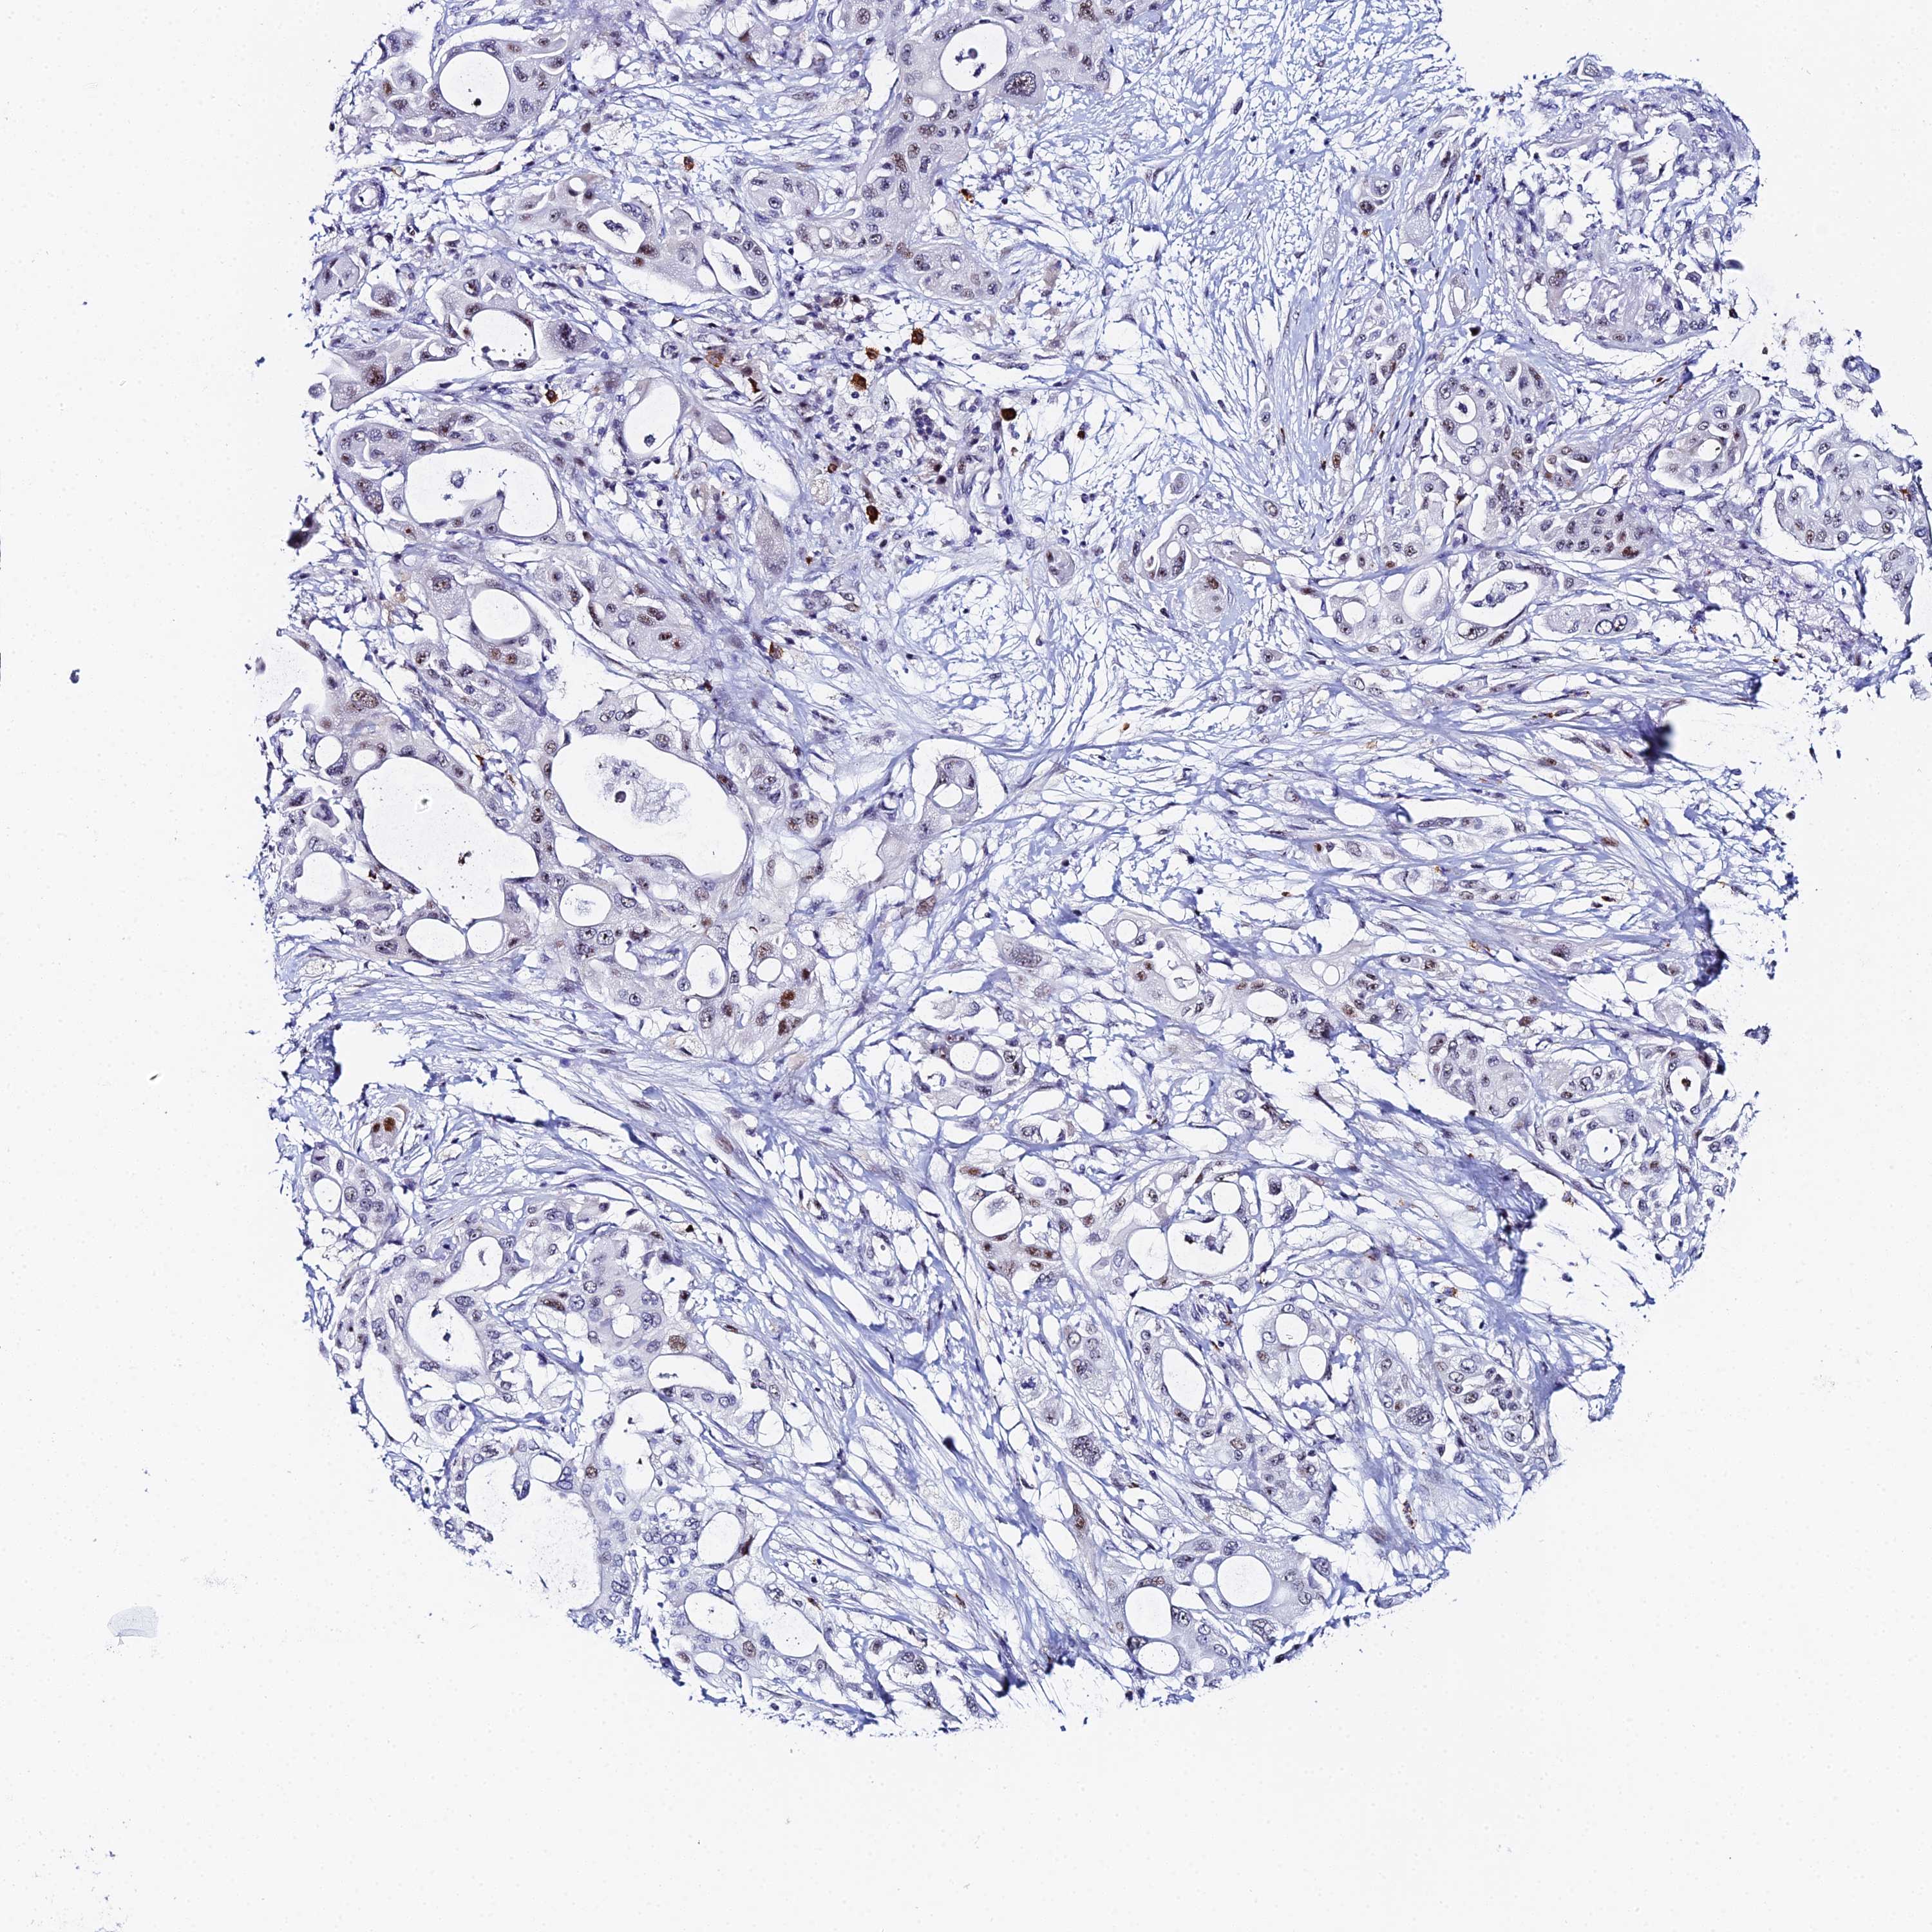

PANCREATIC CANCER - Protein expressioni

A mouse-over function shows sample information and annotation data. Click on an image to view it in a full screen mode. Samples can be filtered based on level of antibody staining by selecting one or several of the following categories: high, medium, low and not detected. The assay and annotation is described here.

Note that samples used for immunohistochemistry by the Human Protein Atlas do not correspond to samples in the TCGA dataset.

Antibody stainingi

Antibody staining in the annotated cell types in the current human tissue is reported as not detected, low, medium, or high, based on conventional immunohistochemistry profiling in selected tissues. This score is based on the combination of the staining intensity and fraction of stained cells.

Each image is clickable and will lead to virtual microscopy that enables deeper exploration of all samples and also displays staining intensity scores, fraction scores and subcellular localization as well as patient and tissue information for each sample.

Antibody HPA045889

Staining

High

Medium

Low

Not detected

Intensity

Strong

Moderate

Weak

Negative

Quantity

>75%

75%-25%

<25%

None

Location

Nuclear

Cytoplasmic/membranous

Cytoplasmic/membranous,nuclear

Adenocarcinoma, NOS